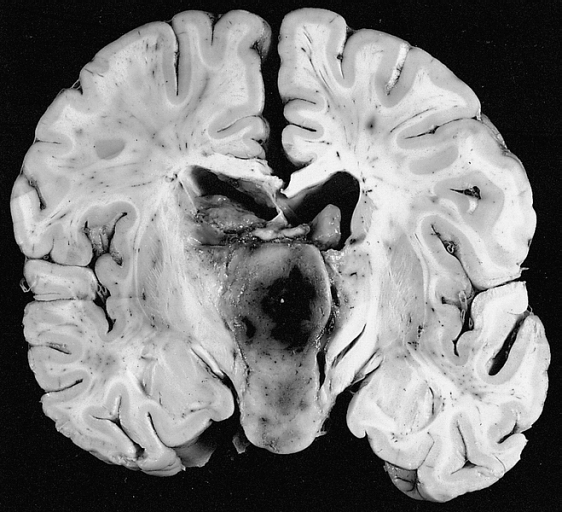

Flowchart of potential head injury rehabilitation services (HI=head injury; rehab=rehabilitation) - Brain Tumors

Brain Tumor